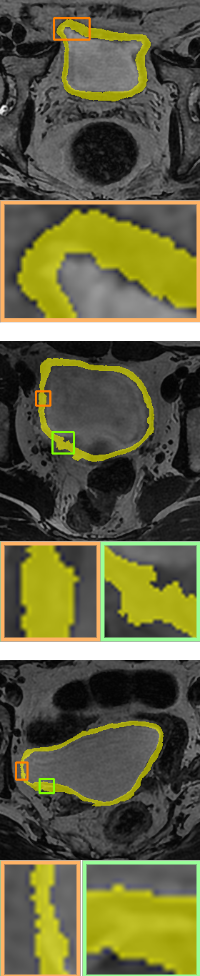

We compare the results of no topological constraints (without-topo), topological constraints without width (PH), and width-aware topological constraints (WT) applied to a number of data-driven models for relevant applications. As can be seen in Table 3, our proposed method (rows with gray background) shows superior performance. Specifically, the improvements in volumetric demonstrate that our method has more accurate result in a pixel-level sense, while the improvements on topology-based metrics demonstrate that WT energy has an overall more precise prediction and topological similarity. For boundary-based indicators, WT performs better compared to PH in most cases due to the width information. The corresponding visualization is given in Fig. 10 and Fig. 11. From the visualization results, it can be seen that in data-driven image segmentation models, no topological constraints will produce obvious topological errors, even if its segmentation results have high accuracy. When constraining topological consistency using persistent homology methods, it may be possible to connect very thin lines to ensure connectivity or a consistent number of holes. We improve the PH method by smoothing the critical points in there structuring elements neighborhood, which can preserve the width information while constraining the topological properties to be consistent.

Ground-truth

Without-topo

PH[ph]

Proposed WT